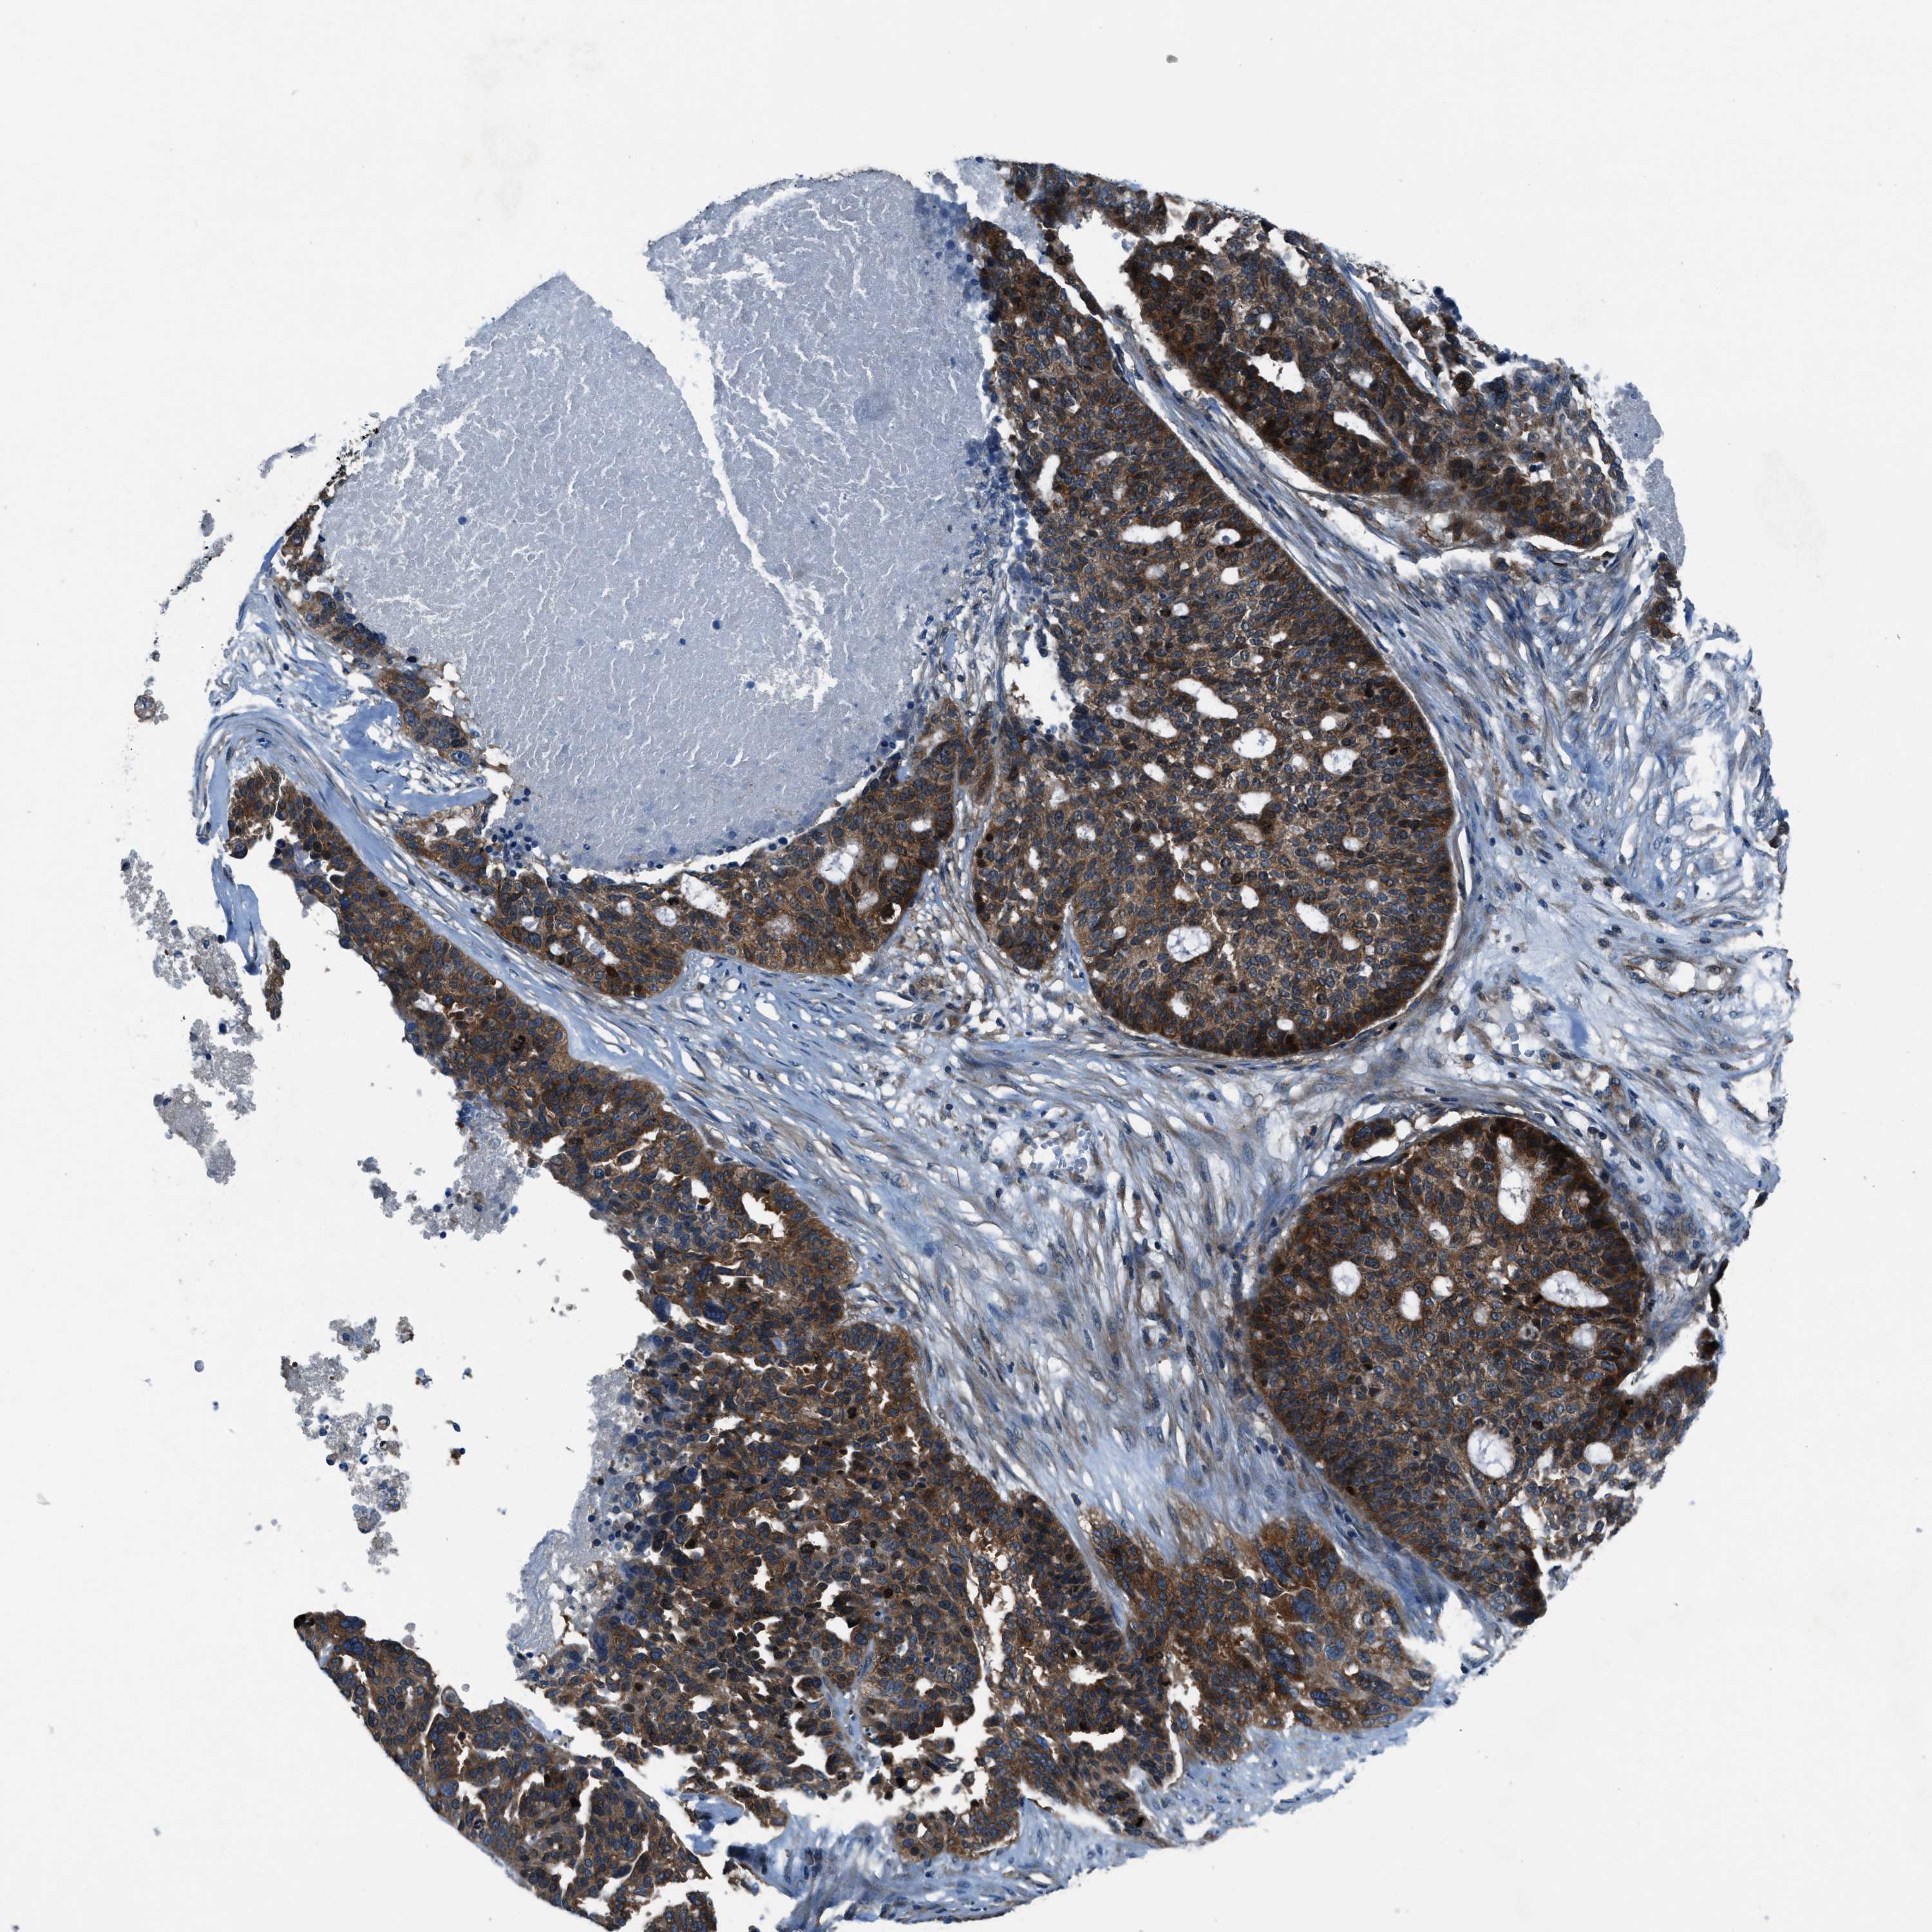

OVARIAN CANCER - Protein expressioni

A mouse-over function shows sample information and annotation data. Click on an image to view it in a full screen mode. Samples can be filtered based on level of antibody staining by selecting one or several of the following categories: high, medium, low and not detected. The assay and annotation is described here.

Note that samples used for immunohistochemistry by the Human Protein Atlas do not correspond to samples in the TCGA dataset.

Antibody stainingi

Antibody staining in the annotated cell types in the current human tissue is reported as not detected, low, medium, or high, based on conventional immunohistochemistry profiling in selected tissues. This score is based on the combination of the staining intensity and fraction of stained cells.

Each image is clickable and will lead to virtual microscopy that enables deeper exploration of all samples and also displays staining intensity scores, fraction scores and subcellular localization as well as patient and tissue information for each sample.

Antibody HPA016649

Antibody HPA018152

Cystadenocarcinoma, serous, NOS

Carcinoma, endometroid

Cystadenocarcinoma, mucinous, NOS

Carcinoma, NOS